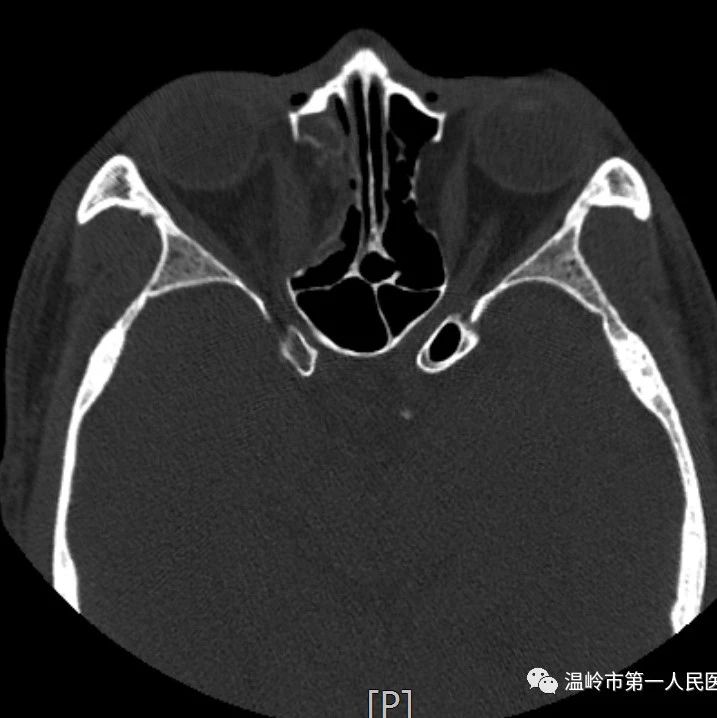

*仅供医学专业人士阅读参考视力下降原来还与这几种疾病有关01甲状腺相关眼病甲状腺相关眼病(TAO)是成年人最常见的眼眶病之一,属于自身免疫性疾病。为区别单纯有眼征与同时伴有甲状腺功能亢进者,习惯上将具有眼部症状同时伴甲状腺功能亢进者称为Graves眼病,而无甲状腺功能亢进及其病史者称眼型Graves病。TAO的三大特点是:眼睑退缩、眼球突出和眼外肌肥大。因每个TAO患者在发病过程中的时间和程度不同,即病变处于活动期或非活动期,眼组织受累的严重程度和部位不一样,故每个患者所出现的症状和体征不完全相同:一些病人有严重的眼球突出而没有眶周肿胀和眼外肌功能异常;另有一些病人有很轻微的眼球突出,但可能有明显的眶周软组织肿胀,畏光、流泪、眼胀痛等,甚至有一些病人开始就有复视而没有明显的眼球突出或眶周痛。...